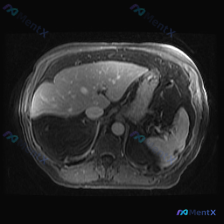

这是一张腹部MRI轴位T1WI图像,影像科的客观描述是这样的:

- 肝脏:信号均匀,边缘光整,未见局灶性异常信号,肝血管清晰;

- 胰腺:体尾部显示清晰,T1WI呈中等偏高信号,胰周脂肪间隙清;

- 脾脏:形态呈新月形,大小正常,实质信号均匀,未见异常信号影;

- 肾脏:皮髓质分界清,未见肿块;

- 胆囊、腹膜后大血管、淋巴结:均未见明显异常,无腹水。

一句话总结:这张图像上,腹部实质脏器(包括脾脏)都没看到明确的局灶性病变。